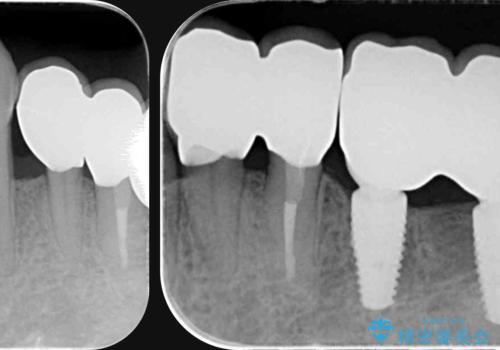

インプラント・ブリッジ補綴を含む、歯周病全顎治療

全体的な歯周病検査を行い、多数の残すことのできない抜歯の必要な歯を認めたため、残せる歯に対しての徹底的な歯周病治療、失った歯に対しブリッジ・インプラント治療を全顎的に行っていくこととしました。